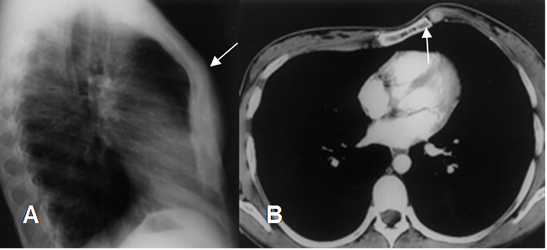

Fig 18. Pectum excavatum.

A: RX lateral. No se encuentran alteraciones significativas en el esternón.

B: TAC axial. Desplazamiento posterior del esternón que comprime la silueta cardiaca y la desplaza hacia la izquierda, por pectum excavatum.